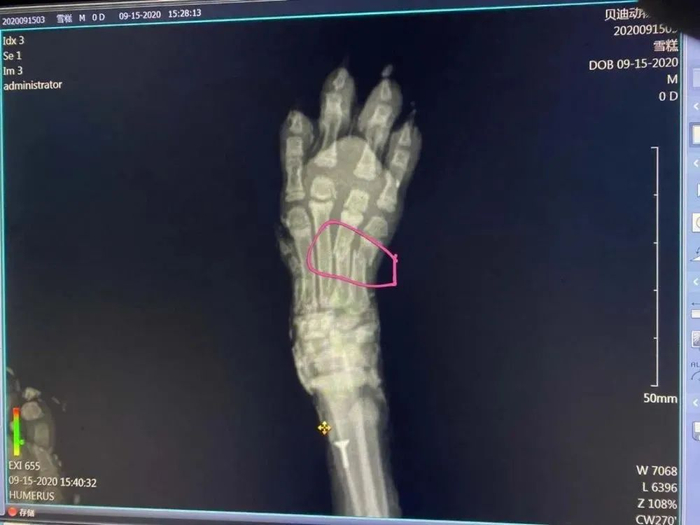

经检查,这只3个月大的小狗

身上裹的是石膏和建筑材料快粘粉

石膏具有腐蚀性,且包裹时间较长

小狗眼角膜已被灼伤,基本失明

医生在剃毛过程中发现

其尾巴断裂,脚掌两处骨折

疑似糊石膏前已被暴力致残